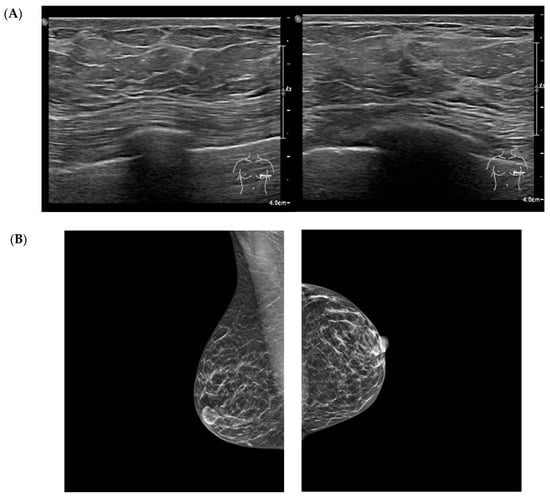

Regarding breast tissue composition, 45% of patients exhibited a predominantly fibro-glandular pattern characterized by a dense fibrous component. Approximately 16% demonstrated a primarily fibro-adipose pattern, while 24% showed a predominantly glandular structure. Representative multimodal breast imaging findings these tissue patterns are shown in Figure 1. Multiple and diffuse breast cysts were identified in 42% of the cohort. Calcifications or microcalcifications—mostly benign and in some cases with dystrophic appearance—were present in 21% of patients. Marked breast asymmetry or tuberous breast morphology was reported in 6%.

Figure 1. Multimodal breast imaging from a patient included in the study cohort. (A) high-frequency breast ultrasound (qualitative illustrative image) shows increased echogenicity of the fibrous septa, finely lobulated adipose architecture, and diffuse stromal thickening without focal lesion. (B) Standard mediolateral oblique and craniocaudal mammography views demonstrate diffuse fibroadipose density, and a homogeneous, non-nodular parenchymal pattern. Images were obtained during routine clinical care and anonymized for research purposes.